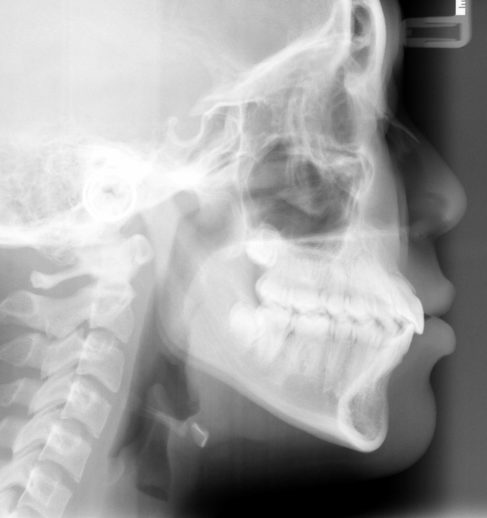

- Radiographs (x-rays) taken from different angles to evaluate jaw and dental growth